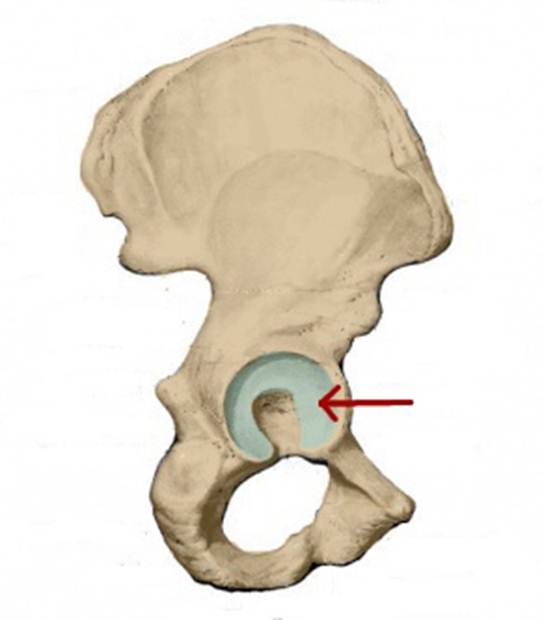

S: На рисунке обозначен art. Coxae (латинский язык).

I:

S: Стрелка указывает на zona orbicularis

I:

S: Стрелка указывает на lig. Ischiofemorale

I:

S: Стрелки указывают на lig. iliofemorale

I:

S: Стрелка указывает на lig. pubofemorale

I:

S: Стрелка указывает на labrum acetabuli

I:

S: Стрелка указывает на lig. Capitis femoris

I:

S: Стрелка указывает на facies lunata